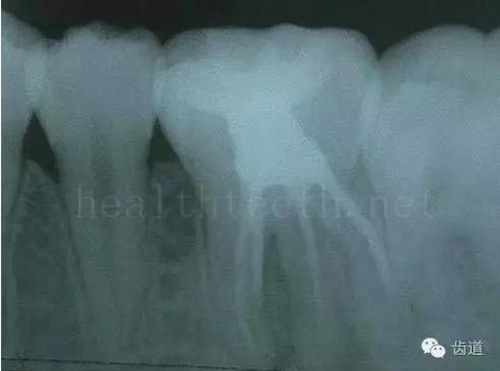

二、牙周組織病

牙片顯示牙槽骨的垂直吸收